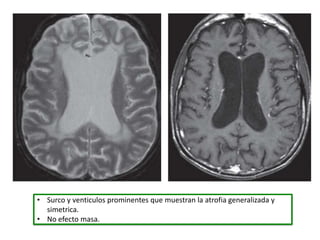

• Surco y venticulos prominentes que muestran la atrofia generalizada y

simetrica.

• No efecto masa.

• Surco yventiculos prominentes que muestran la atrofia generalizada y simetrica. • No efecto masa.